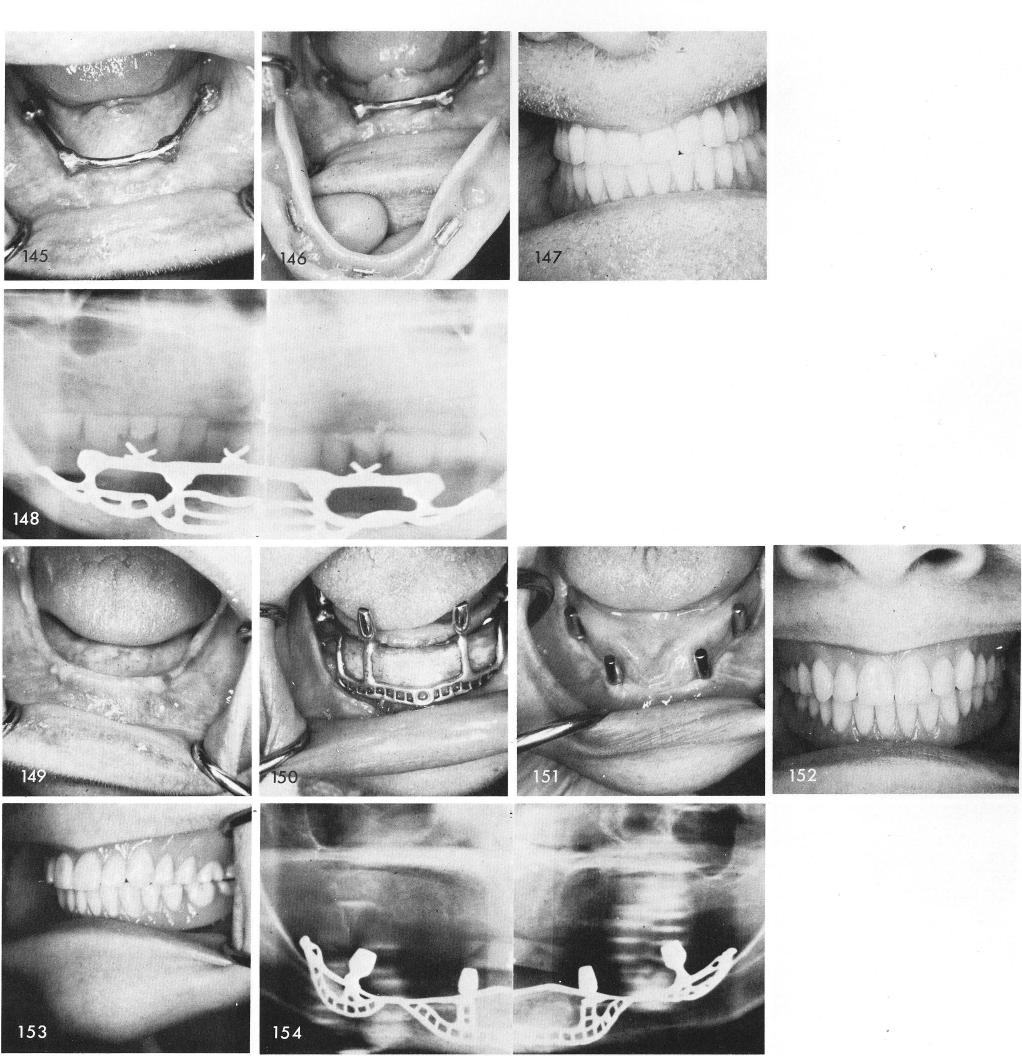

Another case, fig. 149, showing the accurate fit of the subperiosteal framework, fig. 150, and the healing, fig. 151, and completed denture and x-ray, figs. 152, 153, 154.

1 Completed mandibular prosthesis over subperiosteal implant framework